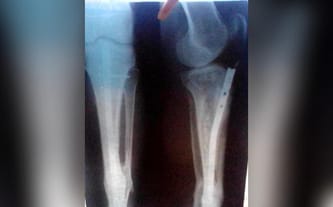

W trakcie pracy przy rozbiórce miałem straszny wypadek i doznałem otwartego złamania nogi. Po pierwszej operacji noga zrosła się nieprawidłowo. Była potrzebna druga operacja, która polegała na zainstalowaniu tytanowego pręta w mojej nodze.

Niestety, pręt ten powoduje ciągły ból i utrudnia mi poruszanie. Ostatnio pojawiły się otwarte rany, które długo się nie goją i istnieje wysokie ryzyko infekcji. Sytuacja staje się niezwykle niebezpieczna, ponieważ występuje zagrożenie złamania kości, co może doprowadzić do amputacji mojej nogi. Bardzo się tego boję!